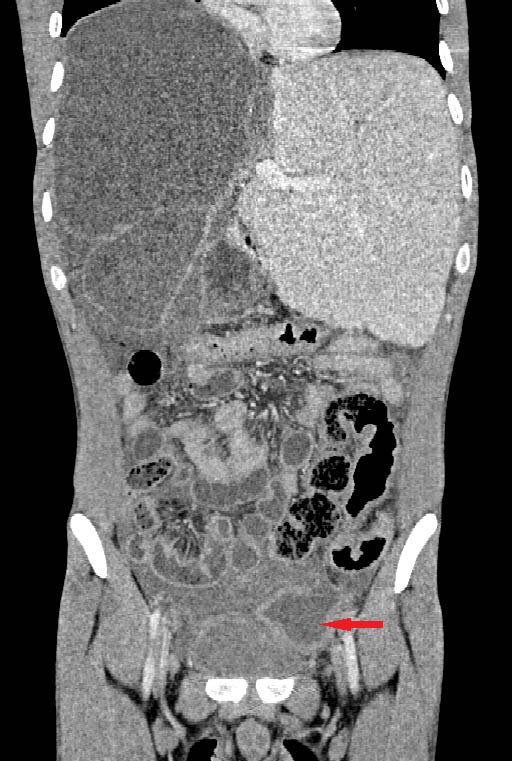

In this study 2 patients of sickle cell disease showed multiple bone infarcts involving iliac bones in addition to the AVN of femoral head. The most common quadrant involved in our study is anterosuperior quadrant seen in 62% of the heads followed by superior quadrant in 27 % cases.

Gabriel et al (5), in their study showed that involvement of anterosuperior quadrant is specific for AVN. Nishii et al (3), in their study showed that location and size of the lesion are the prognostic indicators of collapse and large necrotic lesions have likelihood to involve anterosuperior quadrant.

In this study most common MRI finding of AVN is double line sign seen in 99 femoral heads (85%) which is considered pathognomic of AVN.

Other common findings are contour loss(62%), joint effusion (70%), bone marrow edema(50%), joint space reduction(18%).